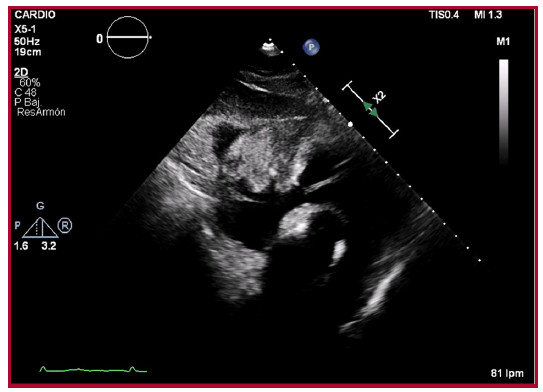

El electrocardiograma (ECG) mostraba ritmo sinusal, a 89 lpm con ondas T negativas de V1-V4, ya presentes en estudios previos. En la analítica se objetivó función renal normal (urea 31 mg/dL, creatinina 0,77 mg/dL, tasa de filtración glomerular 86 ml/ min/1,73 m2) con todos los iones en rango, proteína C reactiva 25,98 mg/L, lactato deshidrogenasa 950 U/L, creatinina kinasa 55 U/L, NT-proBNP 950 pg./mL, troponina T ultrasensible 25 ng/L, hemoglobina 11,2 g/dL, 335000 plaquetas, 11430 leucocitos, dímero D 4860 ng/mL. Para completar el diagnóstico, se realizó una tomografía computarizada (TC) no sincronizada en la que se describía una lesión hipodensa localizada sobre las cavidades cardiacas derechas (Figura 1). Como primera posibilidad diagnóstica se planteó un hemopericardio por rotura cardíaca o dehiscencia del bypass, siendo probable también el diagnóstico de una neoplasia. Ante estos hallazgos, se solicitó valoración por Cardiología. En el ecocardiograma (ETT) se objetivó una masa sólida y heterogénea en el saco pericárdico anterior, con adherencias en las cavidades derechas y compresión del surco auriculoventricular derecho, que no captaba contraste ecocardiográfico (Figura 2). El cuadro no impresionaba una rotura cardíaca, no solo por los hallazgos ecocardiográficos, también porque no había presentado dolor torácico ni alteraciones sugestivas de isquemia aguda en el ECG, y se encontraba hemodinámicamente estable, lo que, a su vez, hacía poco probable la dehiscencia del bypass.